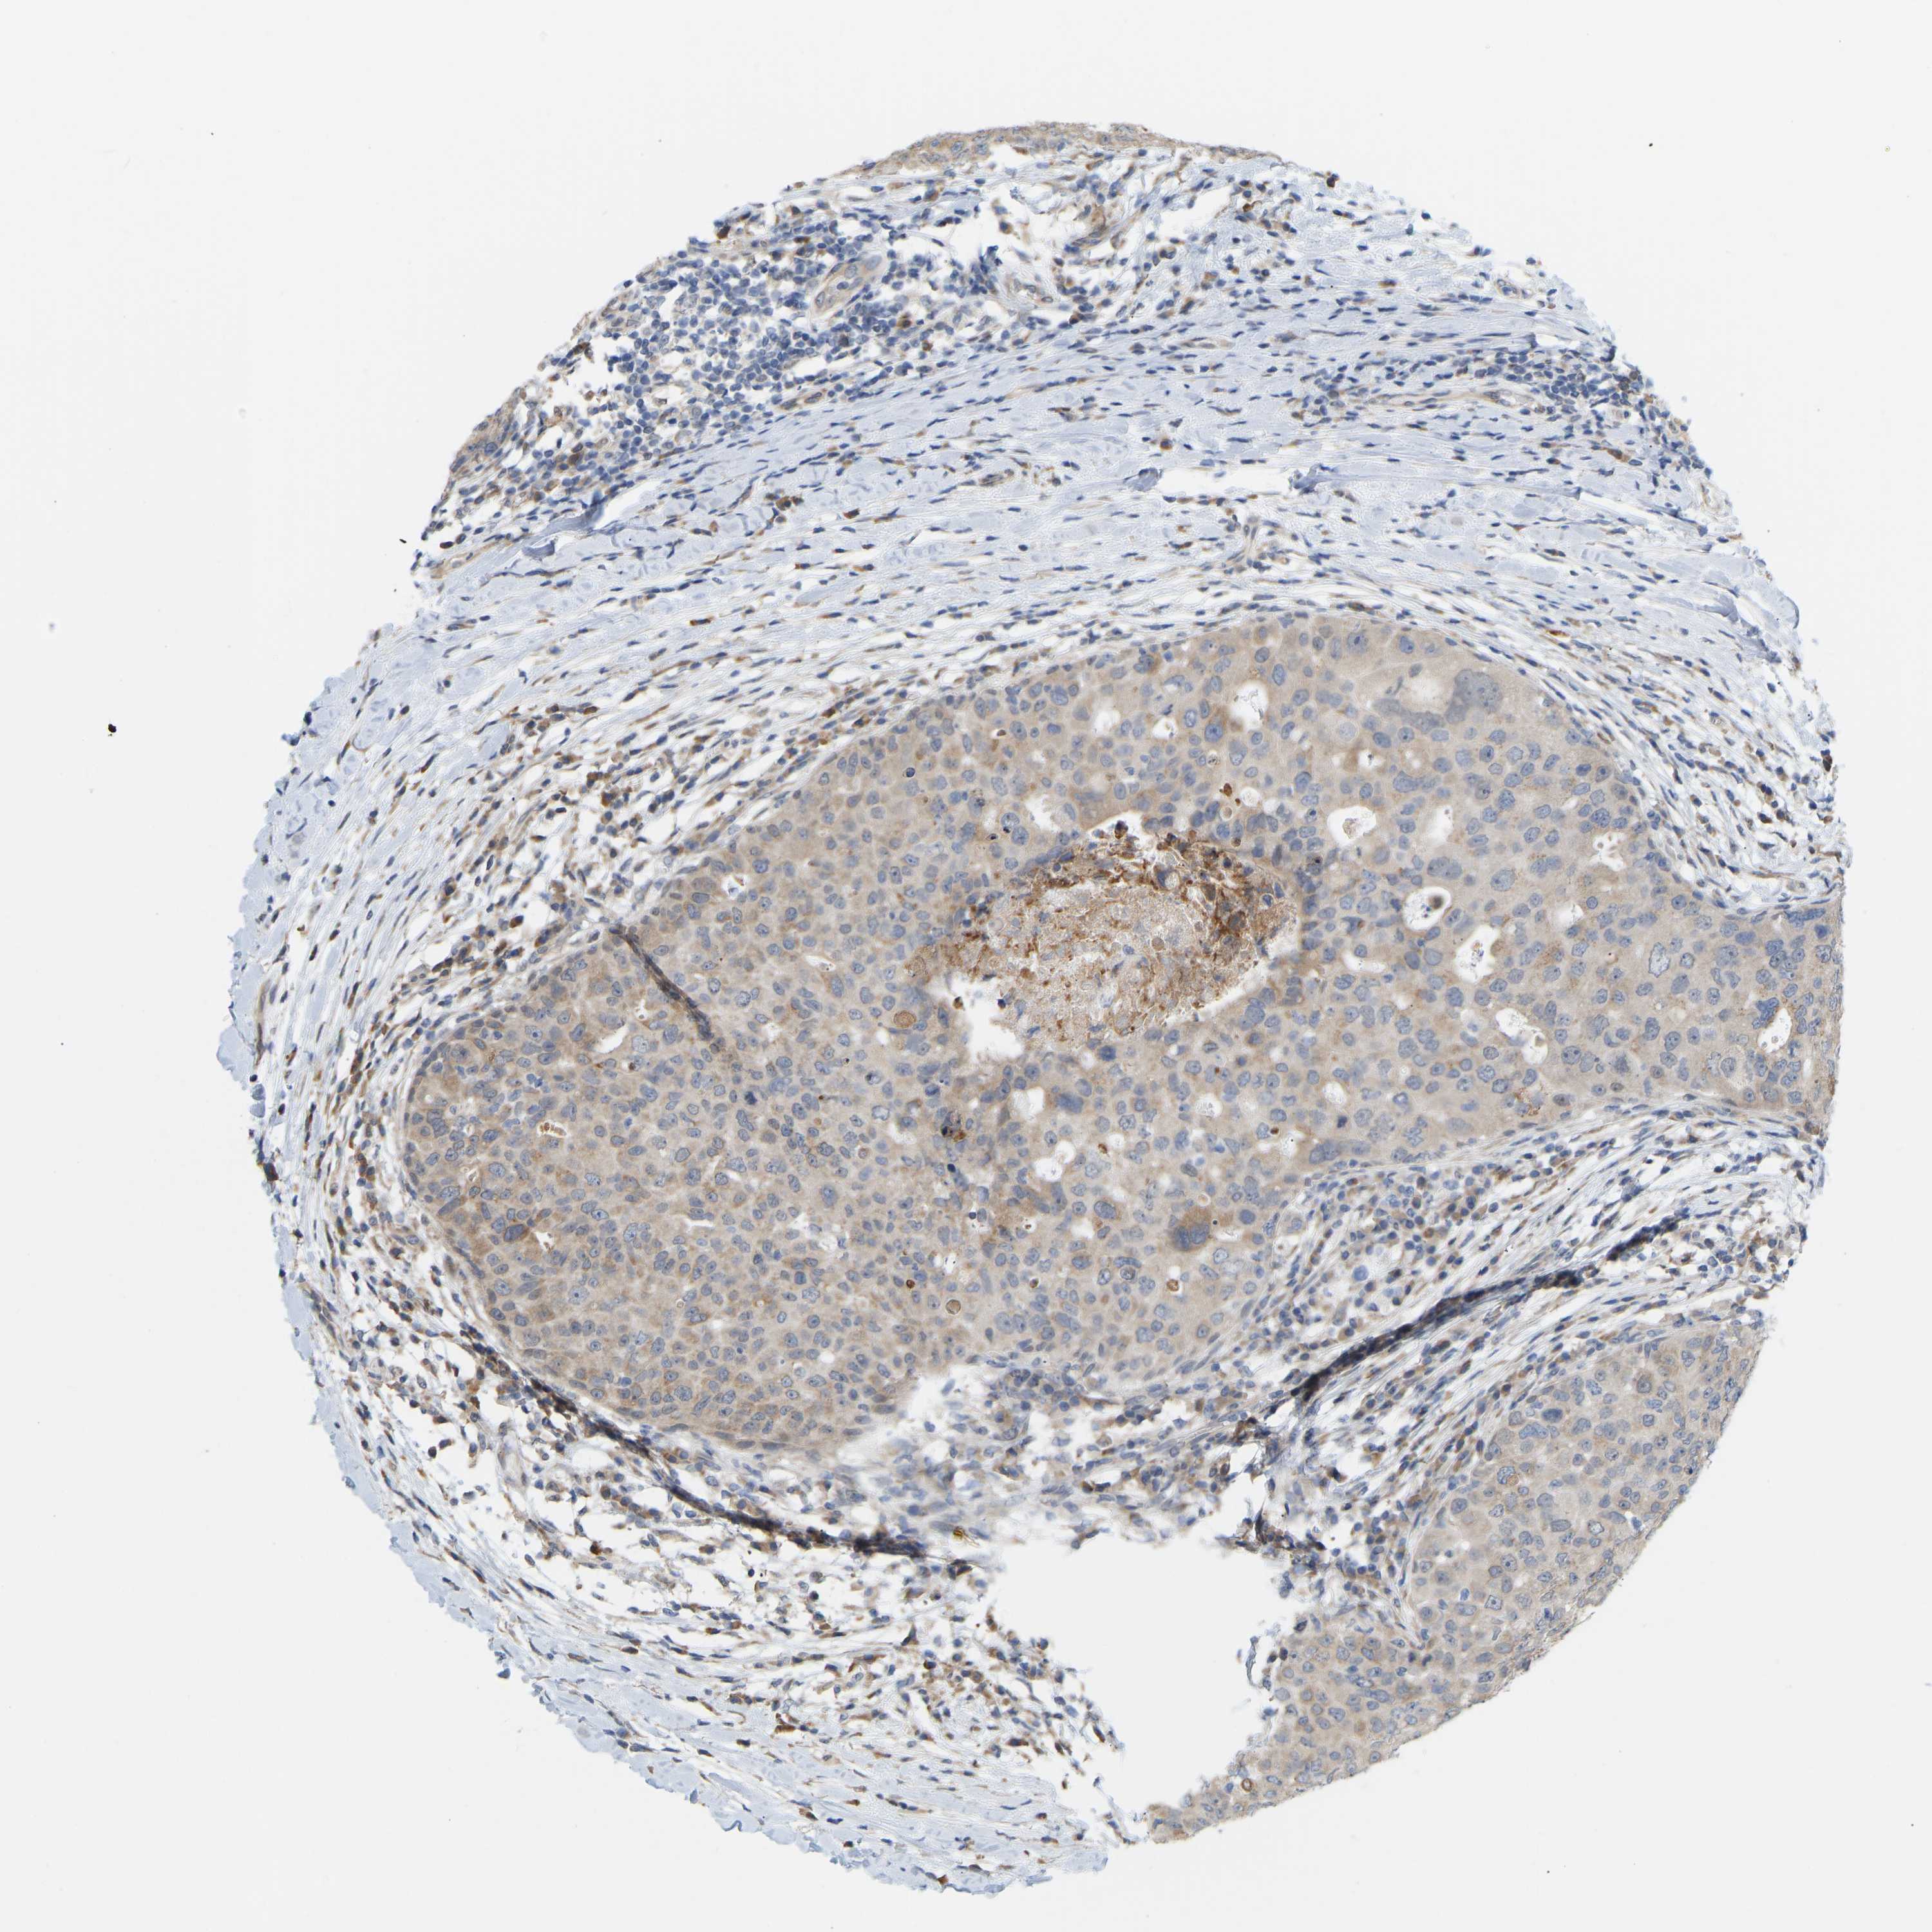

CANCER BREAST CANCER Show tissue menu

BRCA TCGA BRCA VALIDATION PROTEIN EXPRESSION